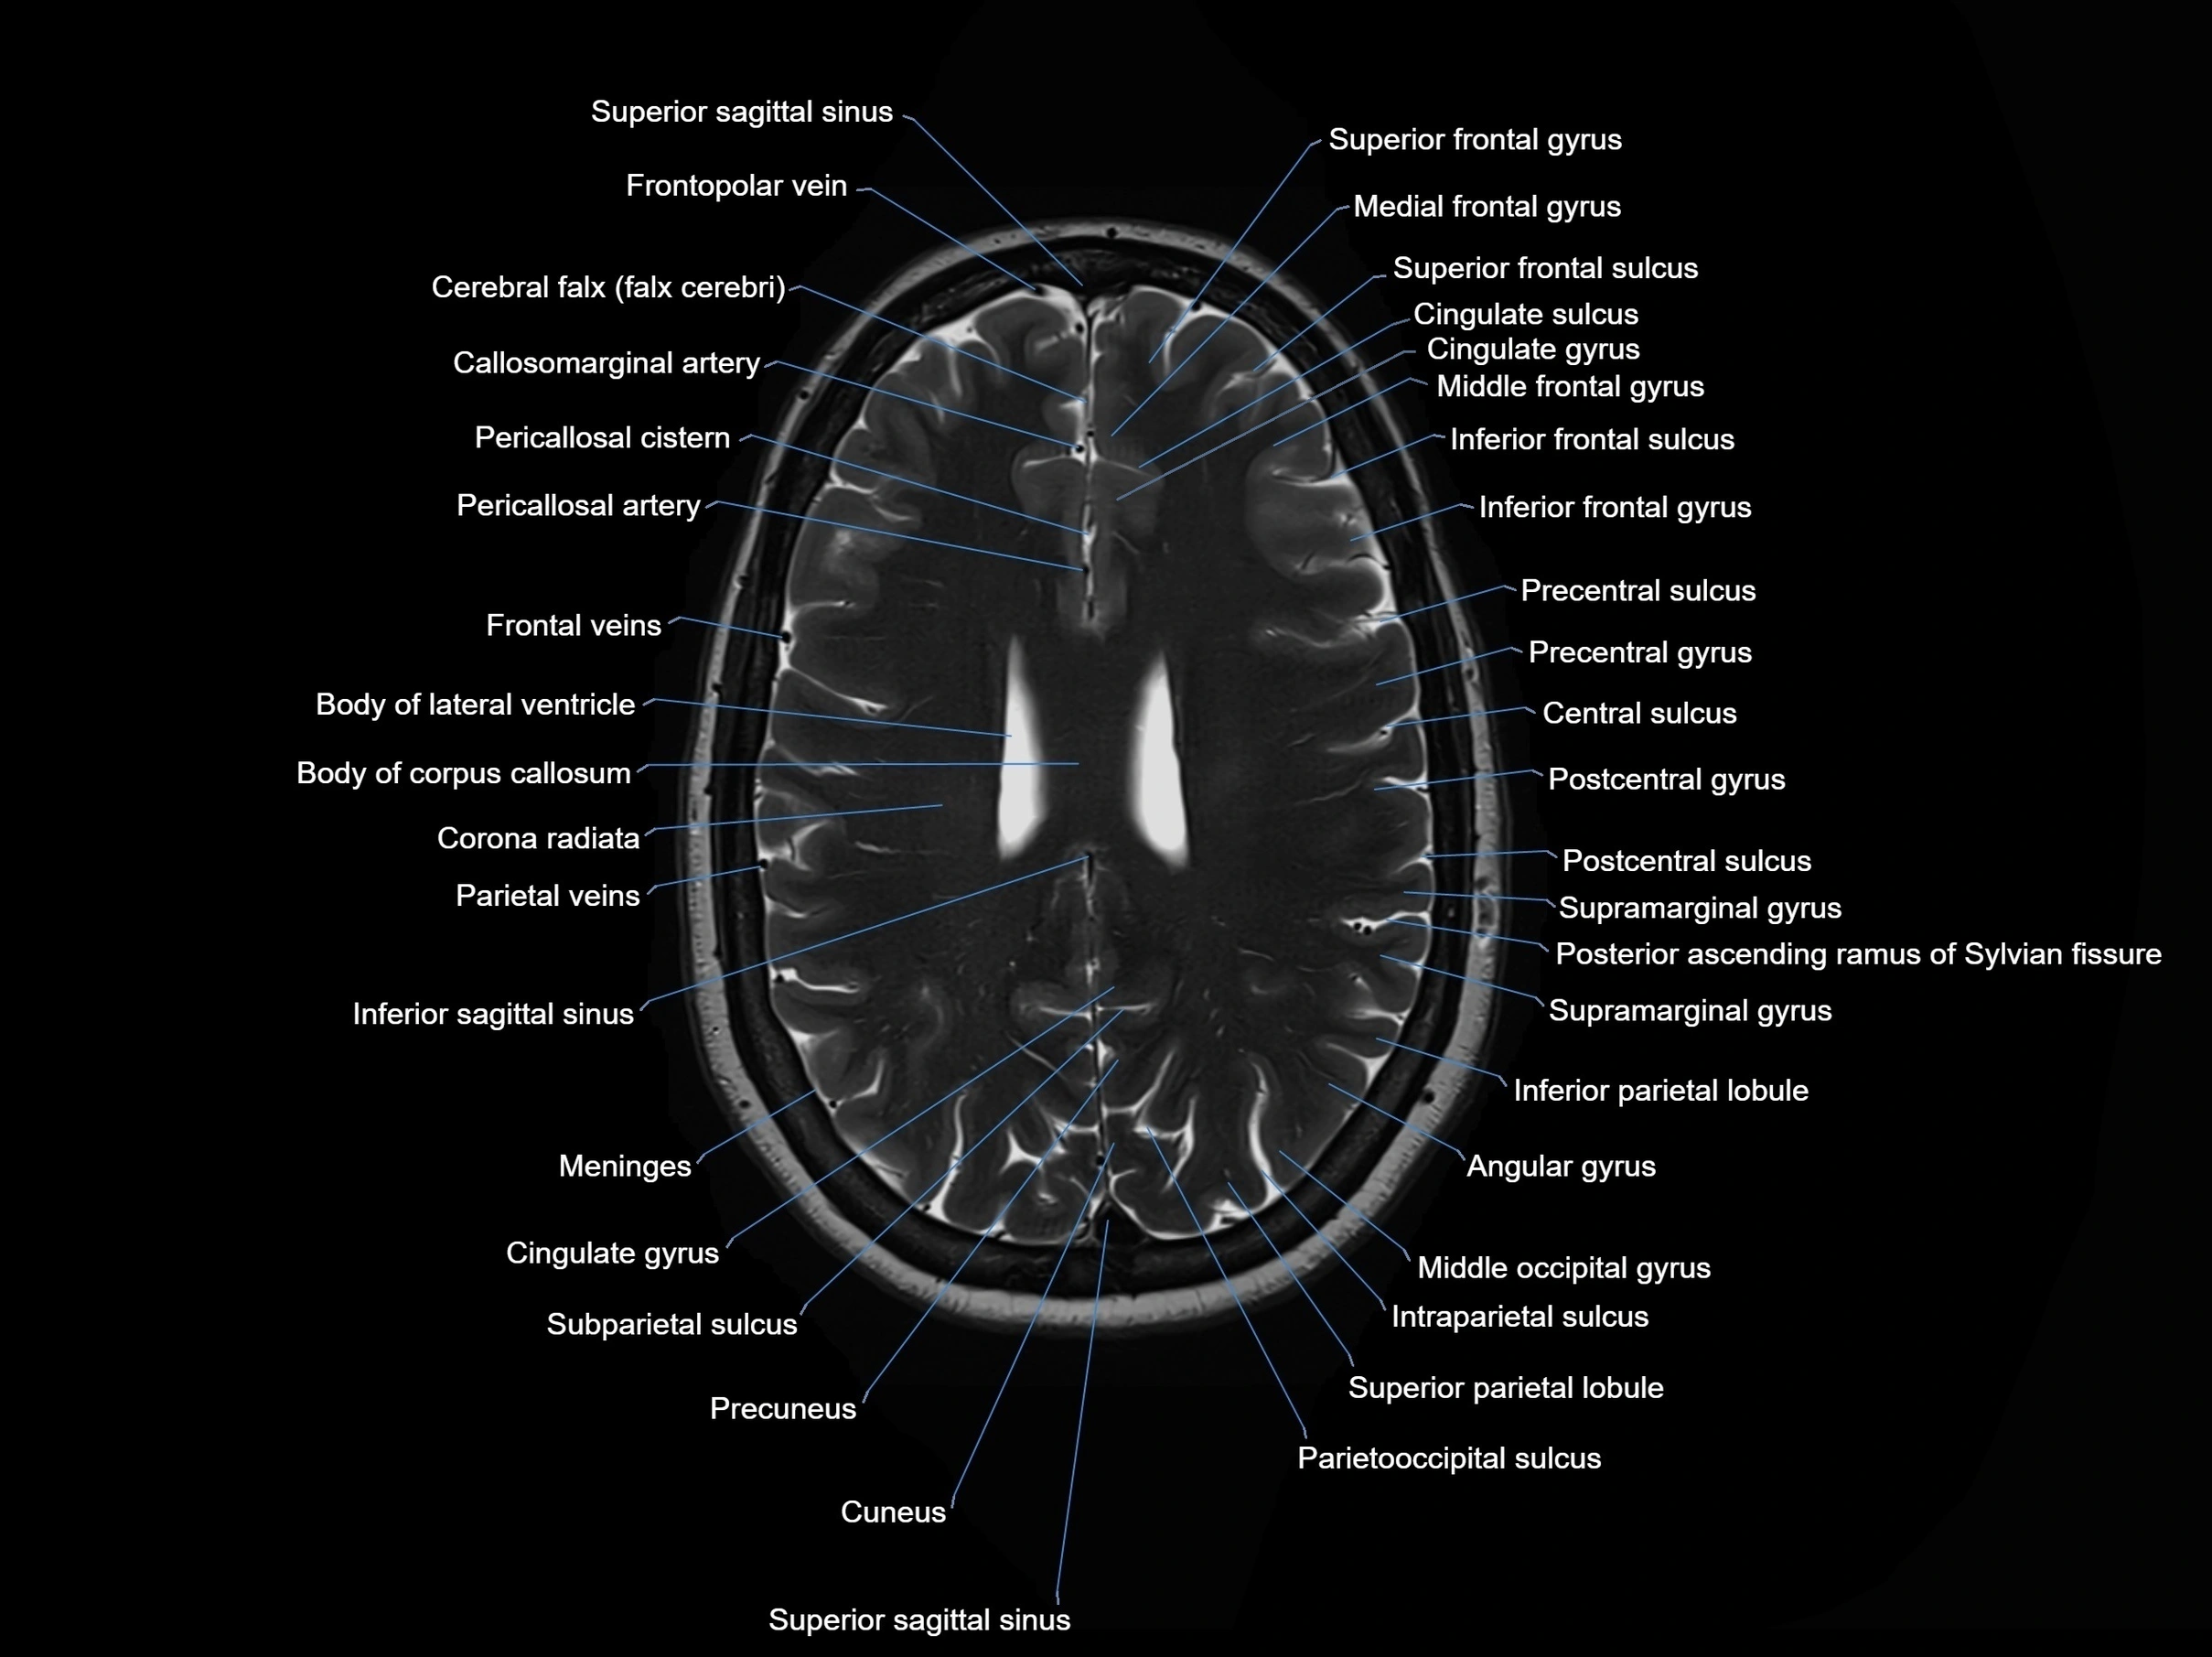

MRI images